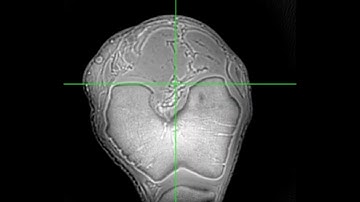

Quantitative Susceptibility Mapping (QSM) High-resolution UTE MRI with Rosette k-space Pattern ISMRM